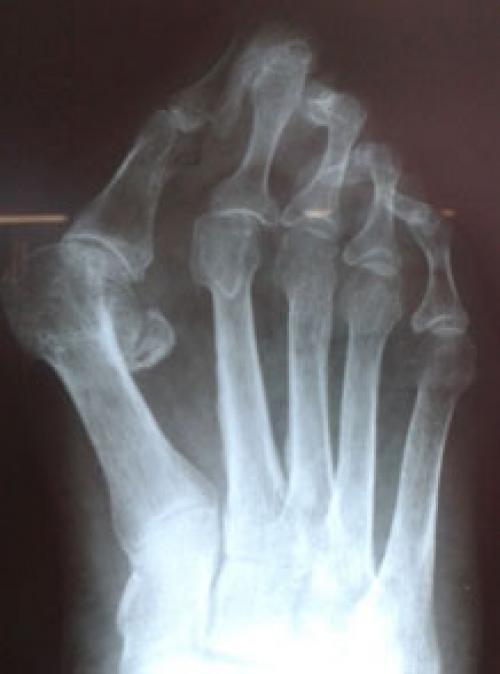

Вальгусное отклонение первого пальца — прогрессирующее дистрофическое заболевание стопы, при котором большой палец отклоняется наружу, а в области его сустава образуется экзостоз или "шишка". Помимо косметического дефекта, деформация приводит к нарушению ходьбы, вызывает боль и часто требует хирургического вмешательства. Пациенты с патологией не могут носить обычную обувь, а на тяжёлых стадиях — и ортопедическую. Это приводит к снижению подвижности и нарушению психологического равновесия больного.

Вальгусное отклонение большого пальца составляет более 70 % от всех ортопедических патологий. Заболеванием в 95 % случаев страдают женщины. Нарушение возникает после 30-40 лет и вызвано гормональными изменениями : яичники вырабатывают меньше половых гормонов — эстрогенов, оказывающих защитное воздействие на соединительную ткань. Соединительная ткань непрерывно обновляется, подвергается перестройке в ответ на нагрузку и повреждение. Структурным компонентом соединительной ткани являются коллагеновые волокна. Основная функция коллагена заключается в том, чтобы придавать соединительной ткани прочность и долговечность. Дефицит эстрогенов ведет к снижению образования коллагена в соединительной ткани. В результате капсульно-связочная система, состоящая из соединительной ткани, теряет прочность.

Клинический осмотр пациента ортопедом, жалобы, рентгенография ступни.

Консервативное лечение